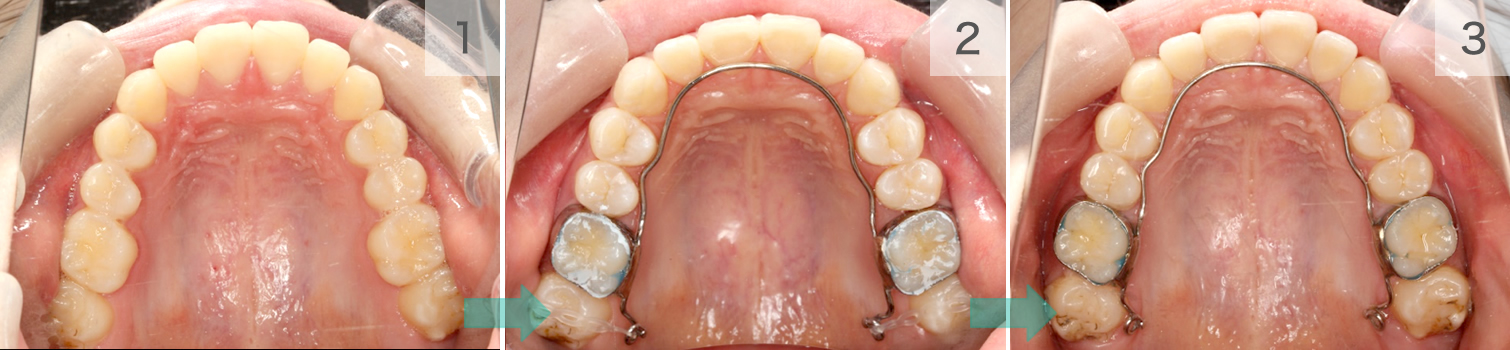

症例07. リンガルアーチ

舌側の主線とバンドで構成されます。

歯列の幅を維持したり、土台にして歯を引っ張ったり、押したりと活躍の場は多いです。

| 治療内容 | 1:最後臼歯が外側に張り出している 2:リンガルアーチ後方のアームから歯を引く 3:歯が内側に移動する |

|---|---|

| 期間 | 半年~1年 |

| 費用 | 300,000円+税 |

| リスク | 磨きづらい箇所は虫歯になるリスクが あります。 |